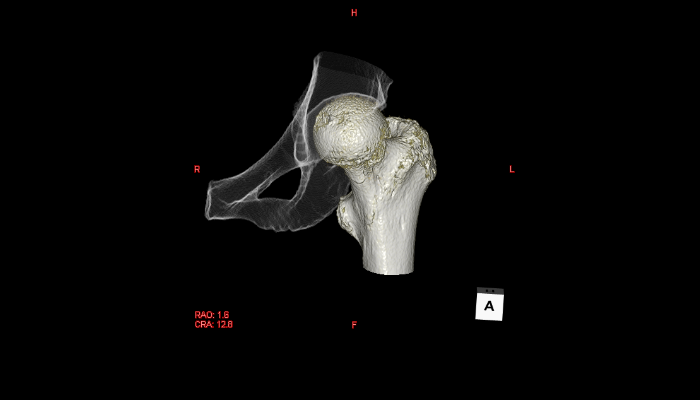

頭部CT画像 頭部CT脳出血や脳挫傷などの評価を行います。 胸部CT画像 胸部CT肺がんや肺炎や大動脈など胸部臓器を評価します。 心臓CT画像 心臓CT冠動脈を評価し、狭心症や心筋梗塞のリスクを検索します。 腹部CT画像 腹部CT肝臓・胆のう・膵臓・腎臓など腹部の重要臓器を評価します。 骨・関節CT画像 関節・骨CT骨折の評価に優れます。 動静脈CT画像 動脈・静脈CT動脈瘤や閉塞性動脈硬化症、深部静脈血栓症など血管の評価を行います。 大腸CT 大腸CT仮想内視鏡と言われる大腸の3D画像を得ることで苦痛の少ない大腸検査をすることができます。検査前日より検査食と下剤を服用していただきます。